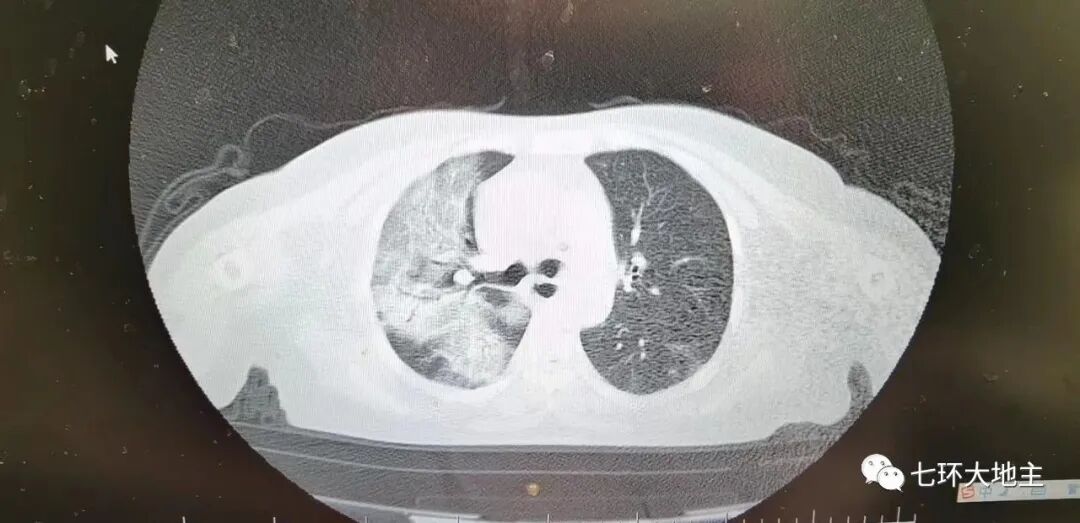

事实上,奥密克戎不但不是专家们说得的小感冒,除了普遍发烧,还出现了不少“白肺”,和2020年疫情爆发初期的症状一样。所谓“白肺”,即肺部出现不同程度的白色浊斑纤维化,是指胸片CT或X光上,肺组织正常是黑色,只有心脏和大血管是白色,但是由于各种疾病、各种致病因素,导致两肺叶呈大片的密度增高,呈现白色。

收入门诊,一扫ct,两个肺白了。

接班看了下病人ct,只感叹华佗再世也没法救,除非肺移植。